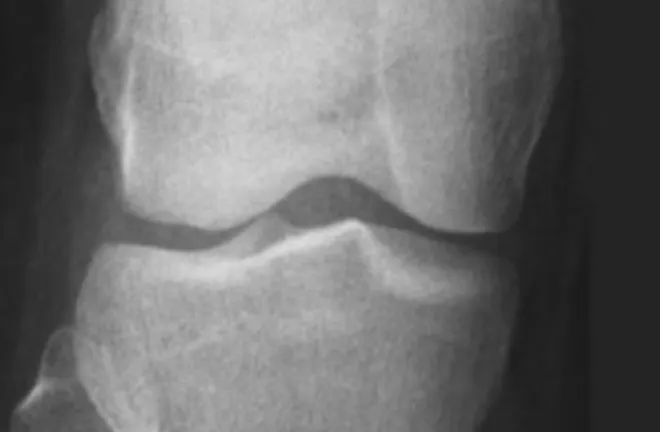

生長板並不是一塊板子,而是形狀類似板子、存在於長骨末端的組織,是一塊由軟骨構成的『區域』,能夠幫助骨骼變長、延伸。在X光影像上「看到」的生長板是一條黑色的縫隙。

(密合的生長板)